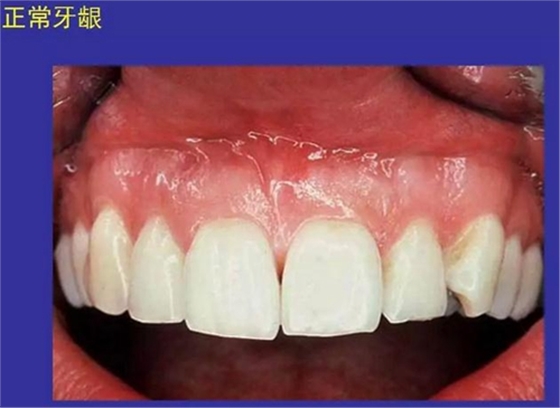

①口腔黏膜(oral mucosa):口腔內(nèi)的濕潤(rùn)襯里